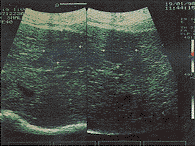

2、HIFU治疗后彩超检测与病理改变 HIFU照射后即刻靶区回声明显增加(图3),解剖大体观:靶区中央可见灰白色凝固性坏死,其周围见暗红色充血区,再外围为苍白色反应带,光镜下可见细胞不可逆性变性坏死。HIFU后1天彩超靶区血供消失、回声增强、边界不太清晰;病检:肝内微血管内皮严重破坏,血管壁塌陷,肝板破坏,肝细胞核固缩。3~7天,靶区回声仍增强,边界清晰,内无血供(图4);病检:靶区呈灰白色改变、质硬、与周围组织界线清晰。光镜下:靶区肝细胞大片坏死,与周围组织分界清楚,在分界处出现炎性细胞、坏死区微小血管破裂。第14天,彩超回声强弱不均,损伤体积缩小;病检:靶区开始收缩、坏死区周围有大量纤维母细胞和新生毛细血管增生。第21天,彩超:体积明显缩小,内部回声以低回声为主;病理:凝固性坏死组织逐渐液化吸收,剖面可见多个或单个小囊腔,壁薄而光滑,内为豆渣样坏死肝组织或清亮液体,镜下见:致密的纤维组织包囊坏死区,并见有大量淋巴细胞浸润。第28天,彩超下损伤区与正常区交界处无显著差异(图5);病检:大体损伤区明显缩小,损伤区基本为新生组织所代替,质地基本与正常肝组织相同,镜下:靶区中心,细胞坏死、自溶,结构完全被破坏,其周边区见假小叶生成,再外围为新生的肝小叶肝细胞形态与排列趋于正常。彩超测定体积与解剖所测损伤区体积基本一致。

治疗区出现强回声光团

图3 在体猪肝HIFU损伤即刻声像图